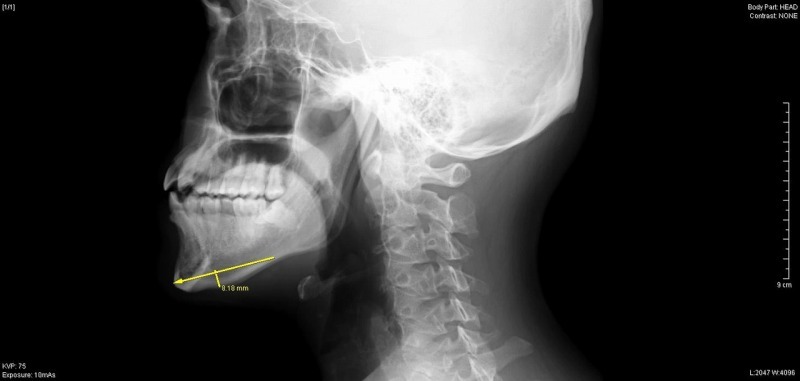

今回は年末に行った、オトガイ形成(顎の骨切り)

について取り上げます。

患者様は、20代 男性で、

顎を短くとがらせたいとの希望でした。

術前のレントゲン検査で最大9mm幅での切除が可能と判断し、

実際も同程度切除が行えました。